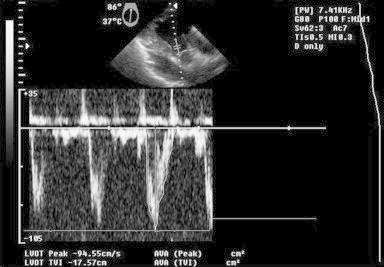

A 37-year-old man living in rural area, presented with history of non-specific chest pain for three months. His physical examination was normal but the chest radiograph displayed a well-defined smooth bulge over left cardiac border and positive hydatid serology (ELISA). The electrocardiogram (ECG) showed non-specific ST–T changes. Transthoracic echo (TTE) showed solitary cystic lesion with honeycomb appearance abutting the left ventricle wall. CT and MRI demonstrated solitary pericardial cyst and ruled out any other organ involvement. Intraoperative TEE findings showed an active lesion – single, multilobulated cystic lesion with well-defined cyst wall and multiple daughter cysts demonstrating ‘rosette’ appearance. Doppler examination did not reveal any alteration in mitral inflow/left ventricle outflow tract velocities ruling out compression and intracavitary communication of the cyst [Figs. 2 and 3, Videos S1 and S2]. Though there was a confusion in case II [Fig. 2, Video 1] regarding whether the cyst is pericardial or intramyocardial on TEE; however lack of a well defined cardiac tissue rim around the cyst, restricted cyst mobility on real time echocardiography favored the pericardial location of cyst which was consistent with preoperative computed tomography and intraoperative findings and was confirmed by post cyst excision TEE [Fig. 4, Video S2].

Fig. 3.

TEE image – deep transgastric long axis view: pulse wave Doppler across left ventricle outflow tract – no compression/impedance to outflow.